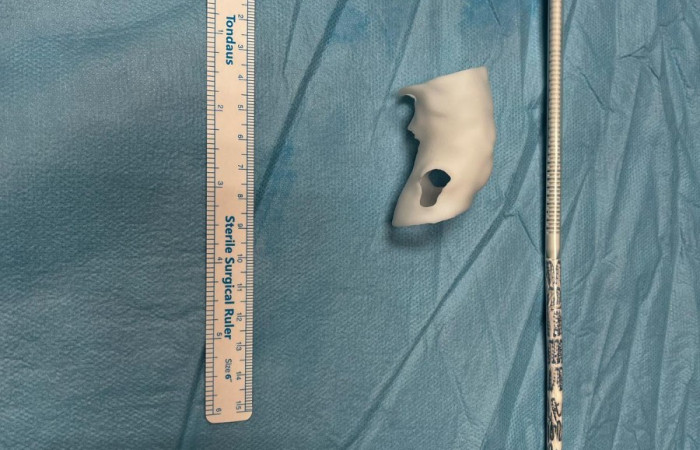

Widoczna na zdjęciach matryca aorty wydrukowana została z żywicy fotopolimerowej, która przeszła proces sterylizacji plazmowej. Użycie technologii 3D umożliwiło indywidualne dostosowanie implantowanego stentgraftu do anatomicznych warunków odejścia naczyń trzewnych od aorty, co z kolei pozwoliło na zakwalifikowanie chorego do małoinwazyjnej procedury zaopatrzenia tętniaka aorty piersiowo brzusznej metodą wewnątrznaczyniową w trybie przyspieszonym.